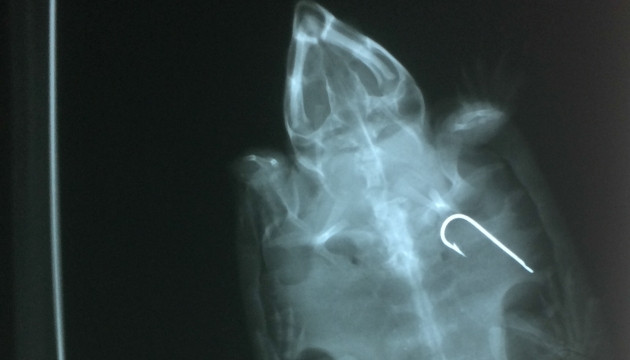

Lưỡi câu nằm trong dạ dày một cá thể rùa đầu to.

Trong đó, 42 cá thể còn sống và 3 cá thể đã chết kể từ vụ tịch thu gần đây được tiến hành chụp X-quang. Các lưỡi câu cá được tìm thấy bên trong hai cá thể rùa đã chết và bốn cá thể còn sống, do đó cần tiến hành phẫu thuật để loại bỏ lưỡi câu trong cơ thể rùa.